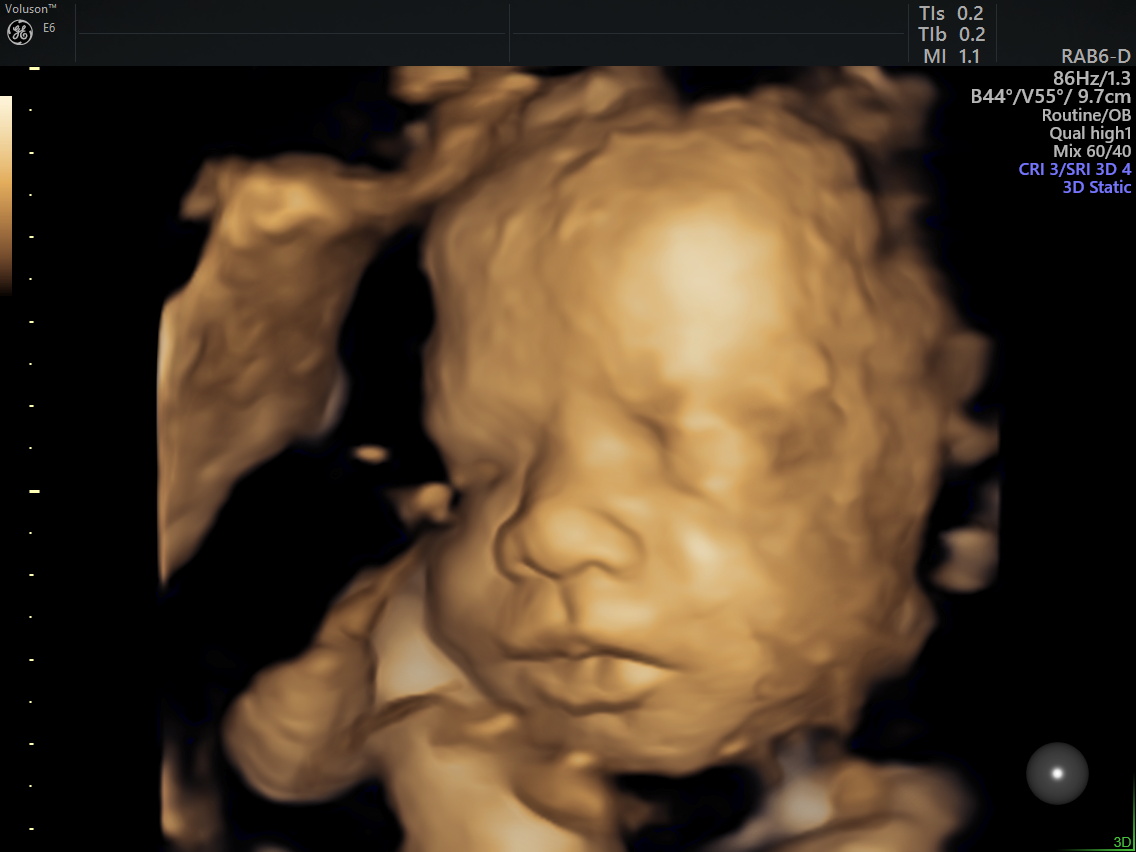

Week 28: This week we had a 3D Ultrasound and it was amazing. Although this is an elective ultrasound (meaning it is not covered by insurance), it was worth every penny. She was a little stubborn at first keeping her arm up by her face and her face buried in the placenta. After a little coaxing and jiggling we got some beautiful shots of our baby girl. I swear she has Krystal’s nose and lips and she is absolutely beautiful. We even got a little smile.